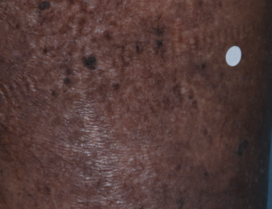

52 YO MALE - calf2

BASELINE

(IGA* = 3, NRS† = 5.86, BSA = 3.5%)

WEEK 2

(IGA = 2, NRS = 1.57, BSA = 1.75%)

WEEK 8

(IGA = 0, NRS = 0, BSA = 0%)

Actual clinical trial participant. Individual results may vary.